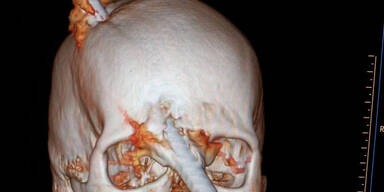

Ein wahres Wunder hat sich in Rio de Janeiro (Brasilien) ereignet: Eine Eisenstange stürzte aus gut 5 Metern Höhe auf den 24-jährigen Bauarbeiter Eduardo Leite. Ein Aufschrei bei seinen Kollegen, als sich die Stange durch seinen Helm hindurch in den Kopf bohrt und zwischen den Augen wieder heraustritt – ein Bild des Horrors!

In einer Notoperation kämpften die Ärzte um das Leben von Eduardo Leite. Sie öffneten den Schädel und entschieden sich, die Stange aus der gleichen Richtung zu entfernen, aus der sie in den Kopf eingedrungen war.